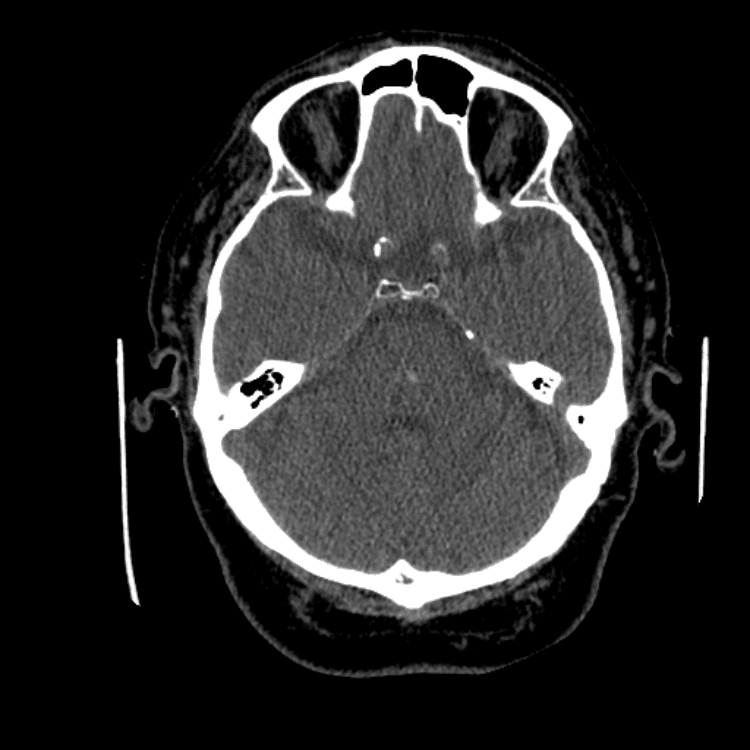

Nontraumatic Brain

Classic